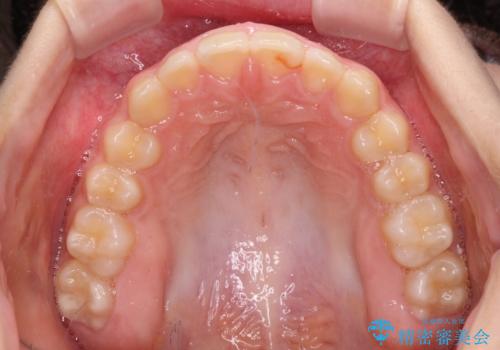

- ヨーロッパにてインビザライン矯正を始めたものの、日本に転居することになり、治療の継続を希望して来院された患者様です。

治療計画に無理がなく、現地担当医と速やかに連絡が取れるとのことで、インビザライン社での転医手続きを行い、継続して治療を行うこととしました。

舌の突出癖により、上下前歯が非接触となっていたため、トレーニングを徹底的に指導し、安定した咬み合わせにより終了させることができました。